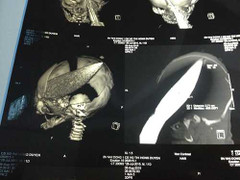

Bé trai 12 ngày tuổi bị đâm xuyên não đã phục hồi sức khỏe và sẽ được xuất viện trong thời gian tới.

(VTC News) – Đến thời điểm hiện tại, tình trạng sức khỏe bé trai 12 ngày tuổi bị kẻ lạ mặt dùng dao đâm thủng não vẫn đang nguy kịch, hôn mê sâu.

(VTC News) – Bé sơ sinh nặng 3kg được cứu sống bằng phương pháp dùng keo sinh học bít dò động, tĩnh mạch não tại bệnh viện Nhi đồng 1, TP.HCM.